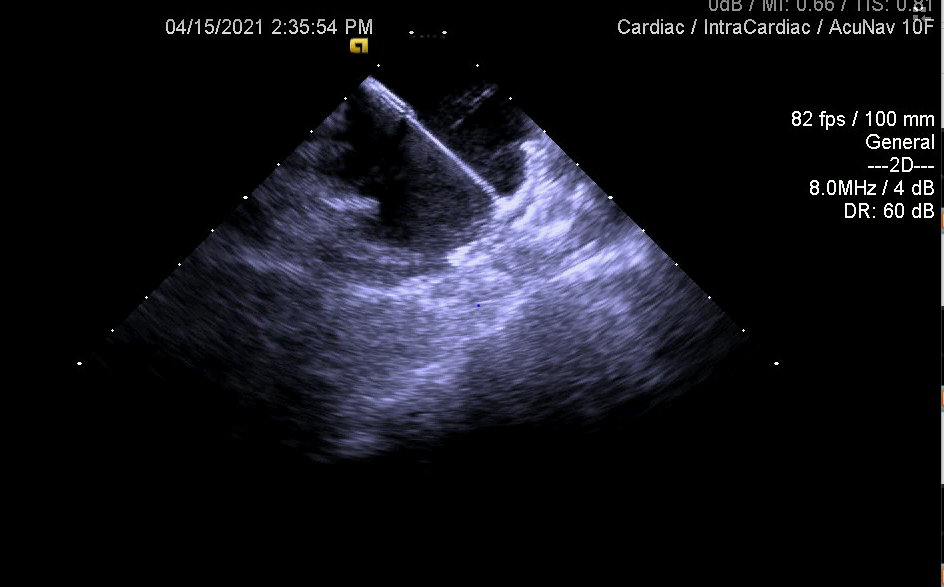

亮点1:心房永存左上腔房颤患者,ICE指导下房间隔穿刺

亮点2:ICE指导术中评估左心耳封堵情况

亮点3:ICE多维度评价左心耳封堵结果—锚定,有无露肩,压缩比测量,有无残余分流